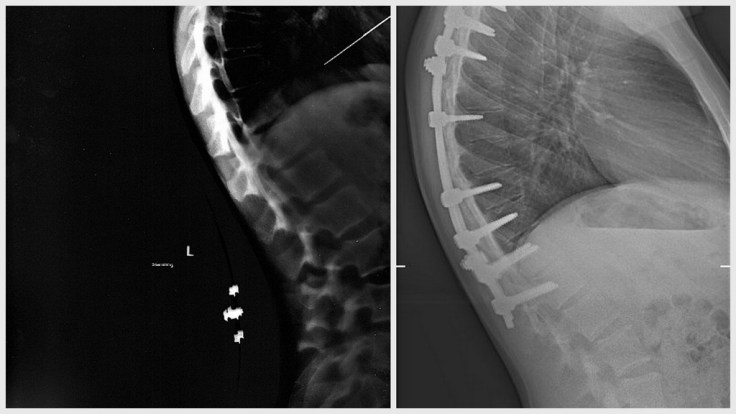

Firstly yesterday Jono had an x-ray done in Merlin Park Hospital in Galway. I have to say they were lovely there, so helpful and efficient. The x-ray at the top right of this post is from yesterday. The one on the left is from 2009 before Jono had his spinal fusion surgery. I wasn’t too sure what to make of this as to me it doesn’t look much different and he was a lot straighter after the surgery.